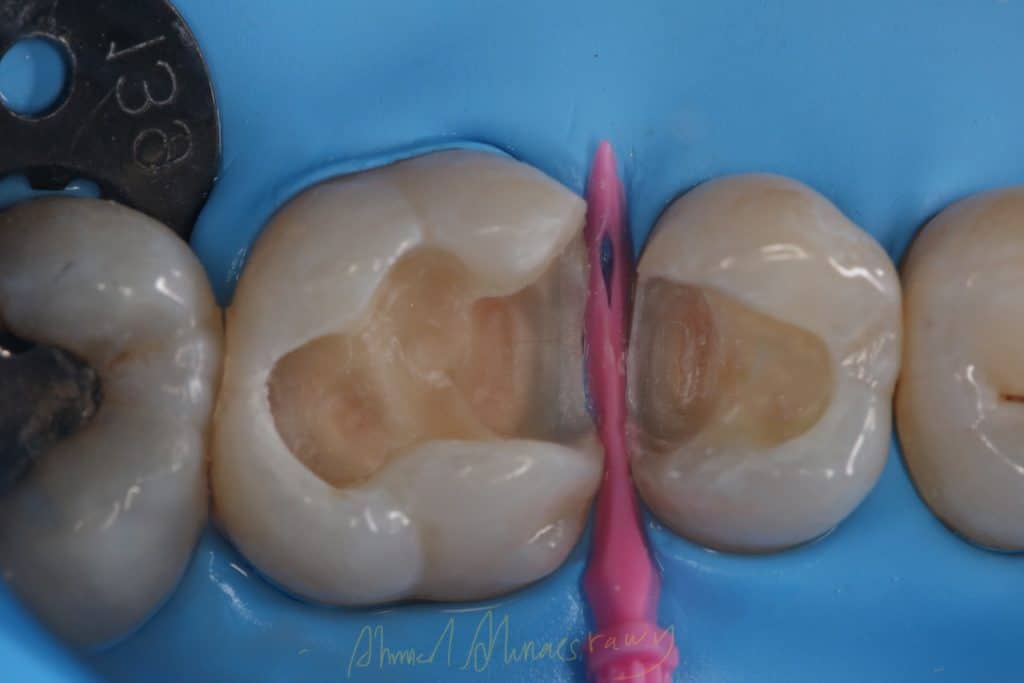

remove old restoration

cavity design

immediate dentin sealing(IDS)

Bioclear matrix system